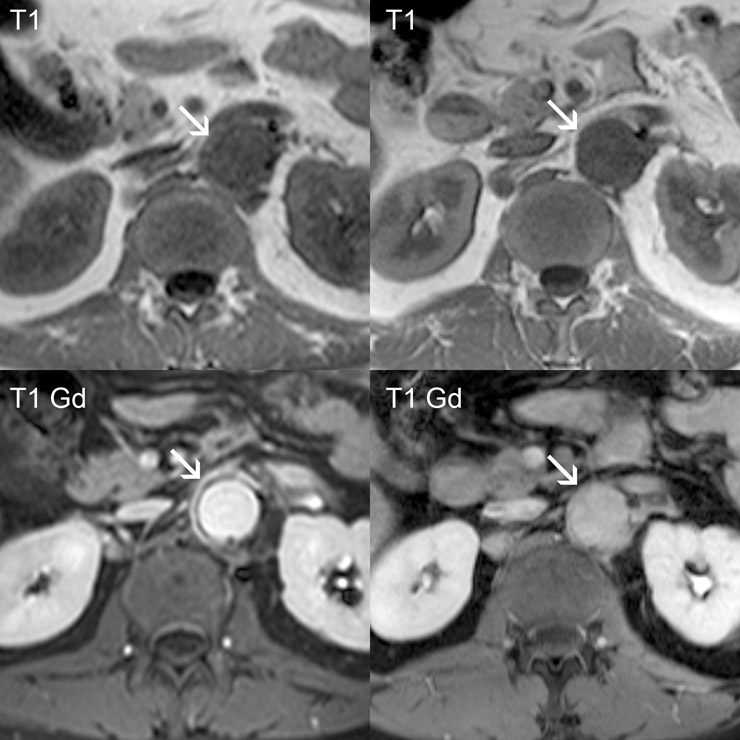

Figure 1

Abdominal magnetic resonance angiography of GCA patient 3 using a 3 Tesla scanner (first exam in the left column, right column after therapy). The inflammatory tissue is depicted as an irregular band with slightly higher signal intensity on non-enhanced T1 weighted images (arrows). After intravenous injection of paramagnetic contrast, this band enhanced conspicuously. After therapy with tocilizumab for three months, the extent of the band decreased and signal intensity after paramagnetic contrast was also considerably lower.

At baseline, before TCZ treatment, five patients presented with constitutional symptoms such as fatigue and malaise, four with polymyalgia, one with jaw claudication, one with amaurosis fugax, one with visual impairment due to opticus neuropathy / anterior opticus ischaemia, one with headache and hyperaesthesia of the scalp, one TA patient with claudicatio of the arms and legs on exercise, and one TA patient with para-aortal leakage of a composite graft placed after acute dissection of the thoracic aorta and ischaemic abdominal pain six years before (table 2). Three GCA and two TA patients exhibited active LVV on MRA, including the thoracic and/or abdominal aorta and its branches. All patients were followed up at the University Hospital of Bern for a mean TCZ treatment period of 4.3 months (range 3–7 months). In six patients initially presenting with constitutional and vasculitic symptoms, complete remission was achieved within two months after the first TCZ infusion and remission was maintained despite continuous and rapid reduction of systemic GC. The acute phase response (ESR and CRP serum levels) returned to normal in six out of seven patients after the first TCZ infusion, and completely normalised in all patients after three months of treatment (table 2). The five patients exhibiting active LVV on MRA before TCZ treatment showed no changes in vasculitic MRA findings after one month, but improved on MRA follow-up after three months of TCZ treatment in the two TA patients and entirely resolved in the three GCA patients. A representative follow-up MRA of GCA Patient 3 before and three months after initiation of TCZ therapy is shown in figure 1. Continuous reduction of GCs over time was achieved in all patients without any signs of clinical or laboratory relapse of LVV after the fourth TCZ infusion.